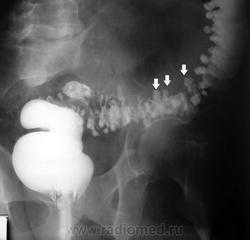

Ирригоскопия по-прежнему является одним из важнейших методов исследования всех отделов толстой кишки. Она дополняет данные колоноскопии и позволяет получить более полную информацию о состоянии органа. Одно из самых частых показаний к ирригоскопии – диагностика рака толстой кишки, полипов и дивертикулов. При ирригоскопии рак толстой кишки виден как дефект наполнения с четкой границей между неизмененной слизистой оболочкой и опухолью; выявляются признаки ригидности кишечной стенки. Нередко участок опухолевого поражения вызывает циркулярное сужение просвета кишки (симптом «яблочного огрызка»). Рентгенологические проявления рака толстой кишки зависят от гистологической формы опухоли, локализации и степени ее распространения. МСКТ и в особенности методика КТ-колонографии могут служить альтернативой ирригоскопии в скрининге и диагностике рака толстой кишки. КТ позволяет лучше видеть изменения кишечной стенки и стадировать заболевание.

Для диагностики ранних стадий рака прямой и сигмовидной кишки стало применяться и трансректальное УЗИ.